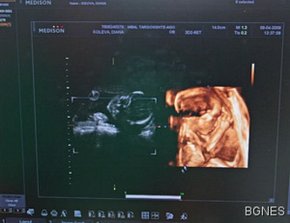

Бременните жени, заразени с вируса на свинския грип, са четири пъти по-податливи на сериозни заболявания, които изискват хоспитализация спрямо останалите хора, заразени с вируса, сочат данните от американско проучване, цитирано от БГНЕС.

При бременните жени е повишен рискът от летален изход при наличието на свински или сезонен грип, но въпреки това само 15% от тях в САЩ следват съветите на Центъра за контрол и превенция на заболяванията (CDC) да се ваксинират. Анализираните данни от проучването на CDC показват, че има 34 потвърдени случая на бременни жени, заразени с (A) H1N1 в САЩ между средата на април и средата на май. 11 от тях или 1/3 от общия брой са били приети в болница. Съединените щати са потвърдили общо 302 смъртни случая заради свински грип от началото на пандемията, което поставя страната на първо място в света по този показател.